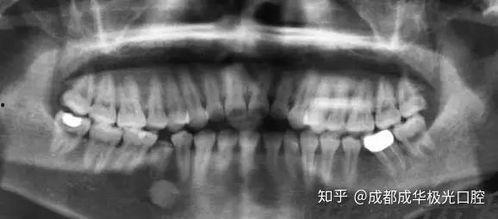

2. X光片:通过X光片,医生可以更清楚地了解你的牙齿结构,以及拔牙的难度和风险。